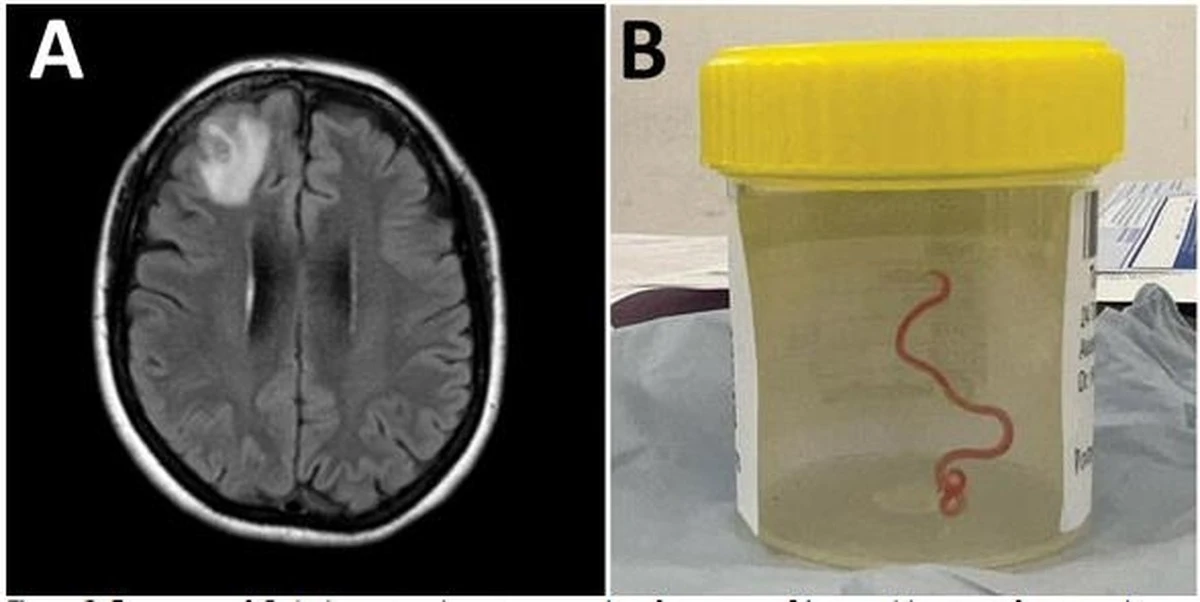

Výsledky odhalily jedinou lézi v pravém čelním laloku. Během operace, která měla tkáň prozkoumat, chirurgové objevili živého, jasně červeného červa. V těle pacienta nebyl nalezen žádný patogen, který by se v něm vyskytoval.

Tento případ byl prvním zdokumentovaným případem lidské infekce tasemnicí druhu Ophidascaris robertsi, parazitickým hlísticí pocházející z australských krajt. Larva o délce 80 mm, odstraněná z pacientčina mozku, představovala patogen, který lidé nikdy předtím neměli.

Během tří měsíců v roce 2022 se u pacientky začala objevovat zapomnětlivost a zhoršení deprese. MRI mozku ukázalo lézii v pravém čelním laloku.

V červnu 2022 chirurgové provedli otevřenou biopsii. V lézi pozorovali vláknitou strukturu a odstranili živého, pohyblivého helmintha (hlístici) o délce 80 mm.

- Histopatologie tkáně ukázala benigní zánětlivou dutinu s výraznou eozinofilií.

- Tým podmíněně identifikoval helmintha jako larvu třetího stadia Ophidascaris robertsi na základě jejího charakteristického červeného zbarvení a přítomnosti tří aktivních retromolárních pysků.

- Nezávislé PCR testování potvrdilo s více než 99,7% shodou identifikaci s izoláty Ophidascaris robertsi.